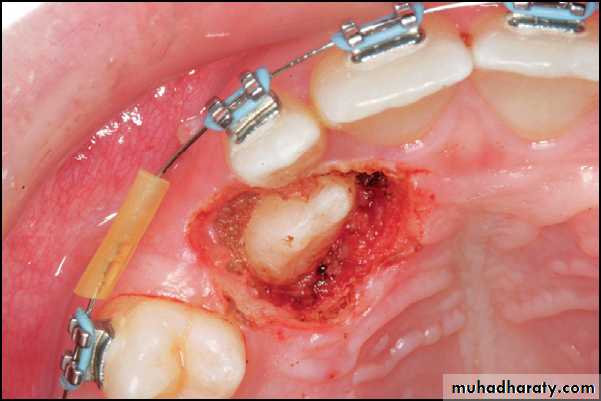

Supernumerary teeth and odontomes often must be removed as they can delay eruption or impede orthodontic tooth movement, particularly of maxillary incisors. If supernumerary teeth are removed from the path of eruption, the underlying teeth will often erupt given sufficient space. It has been estimated that this will occur spontaneously in approximately 60% of cases.An inverted supernumerary tooth—usually referred to as a mesiodens if it occurs in the incisor region. It should only be removed if there is a genuine clinical indication.

Odontomes are less common than supernumerary teeth, although the differentiation between the two is considerably blurred. Odontomes may be simple (tooth-like), compound (multiple tooth-like) or complex composite (containing elements of the tooth germ in a disorganized fashion). Like unerupted teeth, odontomes need only be removed if there are clinical indications (as infection, they are obstructing eruption of other teeth, and esthetic problems).